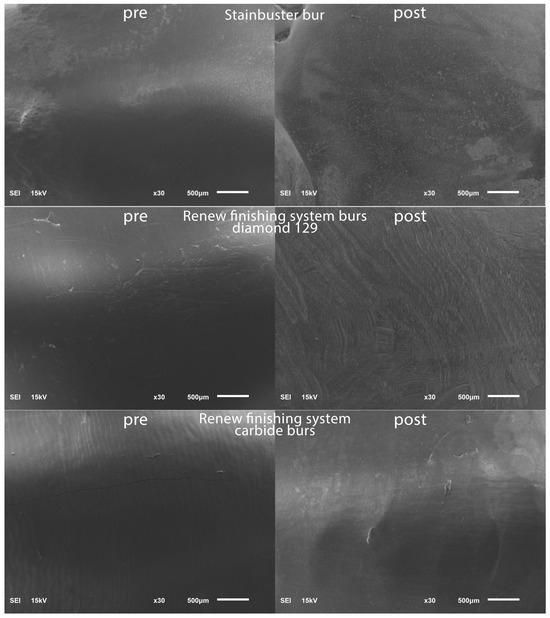

To establish a baseline for the surface roughness data, the teeth were positioned within a vinyl polysiloxane putty mold in preparation for scanning using a scanning electron microscope (SEM) (JSM 6610LV; Jeol, Tokyo, Japan). The SEM parameters employed included 15 kV voltage and a 10 mm working distance. To highlight specific regions of interest on the facial tooth surface, magnifications of 30× were chosen and representative SEM scans were captured in the pre-bracket bonding state; see Figure 1.

Figure 1.

SEM images pre-bracket bonding and post-bracket debonding.

Post-residual cement removal, enamel roughness measurements were performed in a similar routine to the pre-operative enamel surface roughness measurements and representative SEM scans were captured post-bracket debonding; see Figure 1.